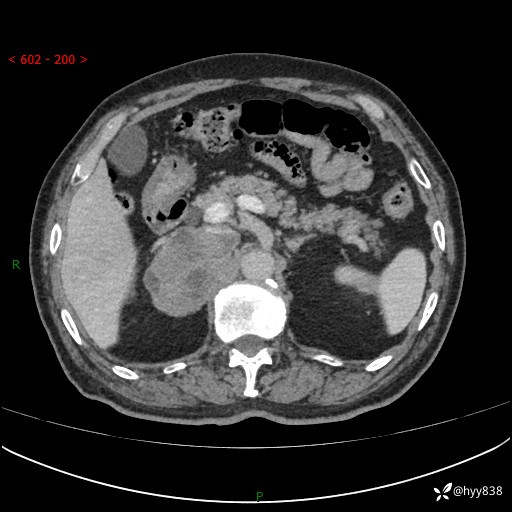

【患者信息】:76岁/男

【主诉】:检查发现右侧肾上腺占位6天

【现病史及既往史】:患者6天前体检发现右侧肾上腺占位,无腰痛,无放射痛,无尿频、尿急、尿痛及肉眼血尿,无畏寒、发热,无恶心、呕吐,今为求进一步治疗,遂来我院就诊,门诊拟“右侧肾上腺占位”收住入院。 起病以来,患者精神、饮食、睡眠可,大小便如常,体力体重无明显变化。

【检查】:肾上腺CT平扫+增强